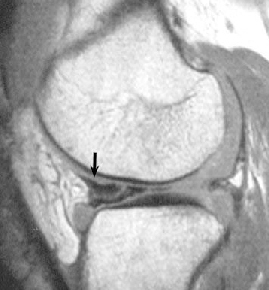

• ACL 손상 방사선 사진4